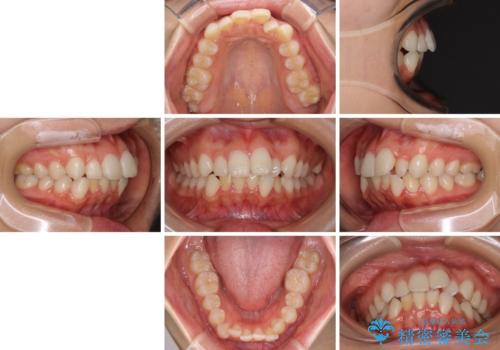

【モニター】前歯のクロスバイトをインビザラインで治療

- 前歯のデコボコとクロスバイトを気にして来院された患者様です。

上顎側切歯(上の真ん中から2番目の歯)が舌側転位している場合、インビザラインでは仕上げきれないことが多く、更には無理して動かそうとすると歯髄壊死を起こすリスクが高いと言われています。

今回は、ワイヤー装置を併用することなく、インビザライン単体で矯正治療を行うこととしました。

インビザライン特有の、奥歯の咬み合わせの問題もなく、しっかりと歯列を改善することができました。

舌側転位している上顎側切歯(内側に引っ込んでいる真ん中から2番目の歯)は、インビザラインが最も移動を苦手とする歯であり、これ以上の改善を望まれる場合にはワイヤー矯正、あるいはワイヤー矯正の併用をお勧めいたします。